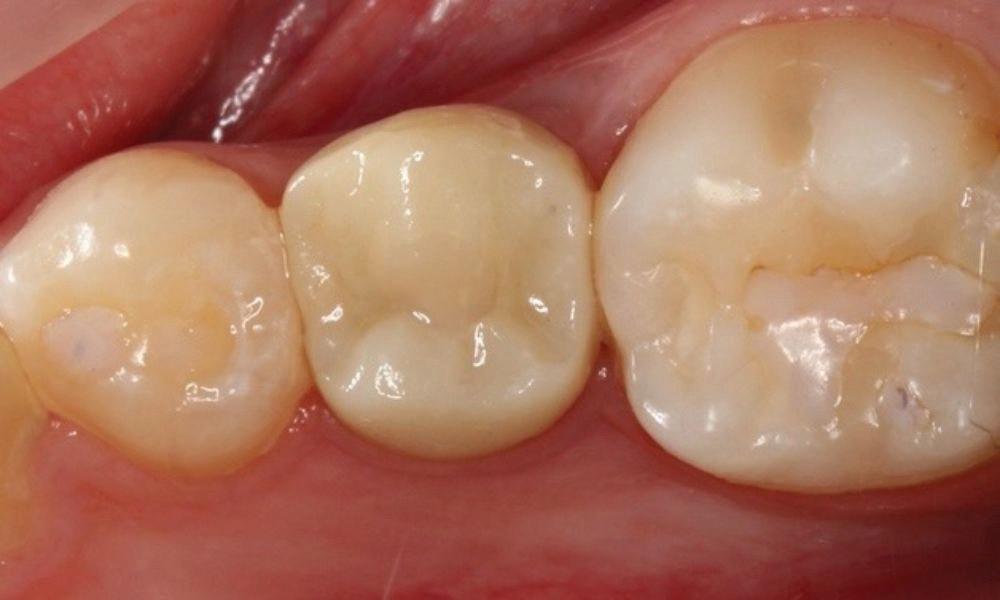

Estelite Asteria (Tokuyama)One of my favourite composite resin materials is Asteria which is a light-cured radiopaque composite for universal use. It considerably simplifies multilayer techniques yet delivers outstanding aesthetics with excellent polishability. Unlike mul tilayer techniques used with conventional composites, Asteria uses only 2 layers for optimal results without compromising aesthetics. The microstructure of the material produces a light diffusion that helps blend in with the natural tooth structure. The chameleon like nature of the material allows a blending of the materials to natural tooth structure and it allows excellent polishability which retains its lustre over time.